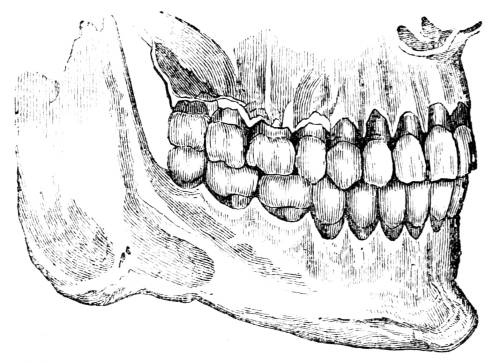

1. The trachea. 2. The right and left bronchus; the left

bronchus showing its division into smaller and smaller

branches in the lung, and the ultimate termination of the

branches in the air vesicles. 3. Right auricle of the heart.

4. Left auricle. 5. Right ventricle. 6. The aorta arising from

the left ventricle, the left ventricle being in this diagram

concealed by the right. 7. Pulmonary artery arising from

the right ventricle and dividing into, 8. The right, and

9. The left branch. The latter is seen dividing into smaller

and smaller branches, and ultimately terminating on the

air vesicles. 10. Branches of one of the pulmonary veins

proceeding from the terminations of the pulmonary artery

on the air vesicles, where together they form the net-work

of vessels termed the Rete Mirabile. 11. Trunk of the

vein on its way to the left auricle of the heart. 12.

Superior vena cava. 13. Inferior vena cava. 14. Air vesicles

magnified. 15. Blood-vessels distributed upon them.

48